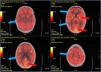

Our patient was a 22-year-old woman errase diagnosed with non-lesional focal right frontal lobe epilepsy at the age of 20 years being seizure-free for the last year treated in monotherapy. In January 2022 she presented COVID-19, with mild flu-like symptoms. Five days after symptom onset, she presented 4 focal to bilateral tonic-clonic seizures and a second antiseizure drug was started. Following this episode, the patient presented severe anxiety, dysphoric mood, and insomnia, and subsequently developed language block, which gradually progressed to motor aphasia, persisting despite adjustment of antiseizure treatment. Two weeks later, she presented 3 focal to bilateral tonic-clonic seizures within several hours, followed by a neurological worsening, developing bradyphrenia and delusions with visual hallucinations and psychomotor agitation; the patient was admitted to hospital. She did not present fever, systemic symptoms, consciousness alterations, or movement disorders. EEG revealed frontal intermittent rhythmic delta activity (FIRDA), with no other relevant findings (Fig. 1). Brain MRI and blood analysis results were normal. We initially suspected seizure control decompensation due to COVID-19, followed by postictal psychosis. The patient was started on benzodiazepines and antipsychotics. Psychiatric symptoms improved and the patient presented no further seizures, but dysphasia and bradyphrenia persisted. Four weeks a lumbar puncture was performed 4 weeks after symptom onset. CSF analysis revealed 7 cells per mm3, with normal protein and glucose levels; CSF cytology and microbiology studies (serology, cultures, PCR) yielded negative results. Anti–NMDA-receptor antibodies tested positive in the CSF and serum. Treatment with methylprednisolone dosed at 1 g/day for 5 days was started, achieving a partial improvement. Subsequently, intravenous immunoglobulins (0.4 g/kg/day for 5 days) were prescribed, gradually improving to her baseline status. A gynaecological examination and whole-body CT and FDG-PET studies were normal, ruling out an occult tumor; however, the FDG-PET study detected diffuse hypometabolism in the cerebral cortex (Fig. 2). The patient was started on rituximab (2 infusions of 1 g, 15 days apart).

Baseline EEG study.

The study was performed with the patient awake, calm, and with her eyes closed. Setup: longitudinal bipolar montage, LFF 0.5 Hz, HFF 30 Hz, sensitivity 10 μV/mm, timebase 15 mm/s. EEG reveals normal background activity with frontal intermittent rhythmic delta activity, both in isolation and in trains lasting several seconds (red line).